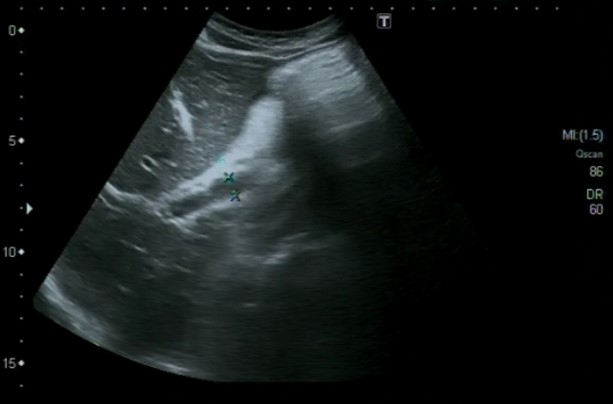

Ecografía abdominal, en la que se identifica abundante cantidad de líquido libre intraperitoneal, a nivel perihepático, periesplénico e interasas, sugestivo de asticis. Hígado, bazo, vía biliar, riñones y vejiga normales.